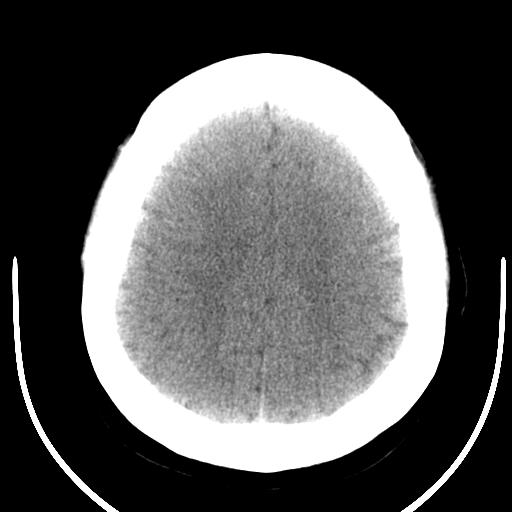

女42岁,从7岁开始就出现癫痫,至今症状不缓解,近几年做过好几次ct 检查,影像上改变不明显。。

病史长,病灶较大,占位效应不明显,脑内肿瘤可能性较小,还是考虑岩骨的或发育畸形吧,性质?骨软骨瘤?血管畸形?做个增强怎样?

赞同楼上的观点,病史长,周围没有水肿,多考虑良性的占位,血管畸形?囊肿?做增强或mri。